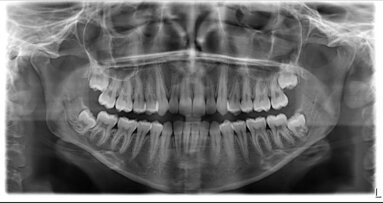

Per aumentare il grado di compliance all’igiene orale nei pazienti non vedenti e ipovedenti è stato pensato un testo scritto in Braille* sull’igiene orale domiciliare da consegnare come ausilio per le persone non vedenti, con l’aiuto ulteriore di una spiegazione a voce. Sono stati selezionati, da un campione di pazienti afferenti al reparto di Igiene Dentale della Clinica Odontostomatologia dell’Ospedale del Circolo di Varese, 6 soggetti non vedenti o ipovedenti collaboranti, tra i 10 e i 90 anni, 3 a conoscenza dell’alfabeto Braille e 3 non con lo scopo di farli partecipare a uno studio in quattro fasi operative per verificarne il grado di compliance.

Prima seduta ‒ Raccolta dati. Per valutare le conoscenze iniziali in tema di salute orale, accertando le abitudini ed eventuali problematiche riscontrate durante l’igiene orale domiciliare. È stato valutato, inoltre, l’indice di igiene orale iniziale tramite rivelatore di placca e consegnato un questionario con domande semplici per avere un’idea delle abitudini e problematiche eventuali.

Seconda seduta ‒ Educazione. Dopo aver eseguito un’igiene orale professionale, consisteva, in una motivazione e istruzione domiciliare con spiegazione a voce di metodi per la cura del cavo orale, integrando la pratica con l’aiuto di un operatore ai pazienti non a conoscenza dell’alfabeto Braille mentre a coloro che ne erano a conoscenza veniva consegnato il testo scritto.

Terza seduta ‒ Rivalutazione. Per determinare l’apprendimento delle nozioni spiegate nella seconda fase, mediante l’esecuzione di un nuovo indice di igiene orale confrontato con quello iniziale. Nella quarta seduta (denominata “Verifica”) sono stati confrontati i miglioramenti percentuali degli indici di placca utilizzando la media aritmetica delle differenze tra indice iniziale e finale.

Ad ogni seduta si è rivalutata la salute orale del paziente mediante indice di igiene orale, il colore delle gengive, la consistenza, il grado di infiammazione, la presenza di depositi molli e duri, di recessioni, abrasioni, ipersensibilità, intasamento alimentare e malocclusione. Si è calcolato poi il PSR dal sondaggio pardontale e compilato il charting.

Dalla ricerca svolta tutti gli aderenti allo studio hanno avuto un miglioramento dal punto di vista dell’apprendimento e nell’igiene orale domiciliare. Il campione dei 6 pazienti è stato sottoposto ad una valutazione del colore della gengiva, margine gengivale, aspetto delle papille e presenza e tipologia di infiammazione e i risultati riassunti in vari grafici da cui risultava che la maggior parte, il 67% presentava gengivite (infiammazione acuta) in atto, delle quali: 75% in forma leggera, 25% moderata e nessuno in forma severa.

Nel restante 33% del campione è stata rilevata una parodontite (infiammazione cronica), 50% nella forma moderata, 50% severa e nessuno nella forma leggera. Il margine gengivale nel 57% dei pazienti aveva un aspetto festonato, nel 29% dei casi presentava delle recessioni e nel 14% vi era un margine ipertrofico. Tutti i casi trattati sono stati valutati come PSR 2 tranne un paziente (PSR 4) trattato come mantenimento avendo subito, da circa sei mesi, un trattamento parodontale chirurgico comprendente levigature a “cielo aperto”.